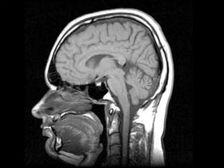

valokuva avoimista lähteistä

Novosibirskin tutkijat ovat kehittäneet lääkkeen, joka tekee ihmisen aivot tuottamaan kantasoluja, jotka ovat tarpeen sairaiden elinten palautumista. “Huume liittyy uudistava, eikä sillä ole analogia maailmassa. Aloitamme tämän vuoden kliiniset tutkimukset, suoritetut prekliiniset tutkimukset “- – sanoi yhtiön hallituksen puheenjohtaja ja omistaja, joka kehitti lääkkeen, Andrei Artamonov. Hänen mukaansa lääke saa aikuisten aivot tuottamaan uusia kantasolut, jotka myöhemmin löytävät vaurioituneen elimen ja palauta se. “Lasten aivot tuottavat aktiivisesti varren soluja, koska vauva kasvaa. Ja aikuisen aivot pystyy tuottamaan niitä, vain hän ei halua tehdä tätä – hänelle sitä ei tarvitse. Lääkkeemme stimuloi oman varren tuotantoa soluja “, Artamonov selitti. Hänen mukaansa kaikki operaatiot kantasoluja tuotetaan nyt ihmiskehon ulkopuolella, joka liittyy tietty riski siitä, että muokattu, keinotekoisesti lisätty solu voi käynnistyä olla vuorovaikutuksessa odottamattomassa paikassa. Soluja voidaan syöttää, mutta se aina riski, koska ei ole kovin selvää missä he ovat eriytetty. Vaikka ne ovat sinun, he levitetään sinun ulkopuolellasi elin. Omat kantasolut eivät voi epäonnistua siellä eriyttää. He löytävät vaurioituneen elimen ja aloittavat tämän palauttaa vartalo “, lisäsi Artamonov. Kliiniset tutkimukset lääke kestää puolitoista vuotta, Interfax raportoi.